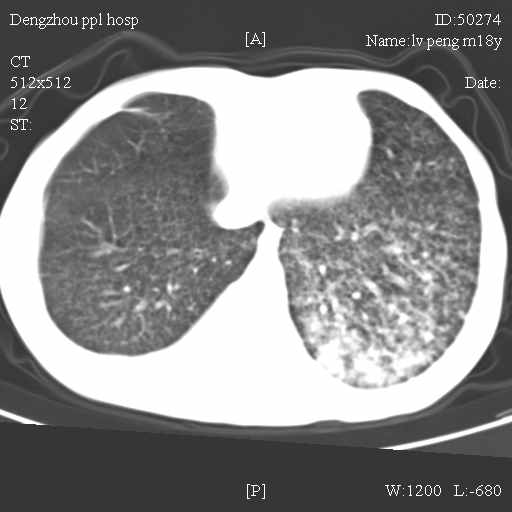

标题: CT10510:男.18岁,咳嗽咳痰两月.(有病理) [打印本页]

标题: CT10510:男.18岁,咳嗽咳痰两月.(有病理)

双肺布满大片状实变及网格状结节影,内参杂大小不等的气囊及空气支气管征,心脏增大。考虑:1 全身结缔组织疾病—系统性红斑狼仓?2 肺泡蛋白沉积症合并感染!

双肺布满大片状实变及网格状结节影,内参杂大小不等的气囊及空气支气管征,双侧胸膜腔少量积液,双下肺近膈面透亮度尚可,病人较年轻,病变较重(不知为什么上胃管?)考虑:1.胶原病肺部改变,2.组织细胞病x。结合实验室检查。

首先考虑组织细胞x病。两肺中上肺野多发囊腔,中下肺野内见多发小结节,并可见肺间质增厚。患者是男性,年龄较小。胶原性病变比较多见的类风湿、系统性红斑狼疮和硬皮病临床和影像均不是很支持,类风湿和系统性红斑狼疮的肺部表现最常见的是胸腔积液,硬皮病可见食管的扩张。

肺内多发斑片状、结节状、融合大片状及网格状影,多发薄壁空腔影,胸膜肥厚,纵隔、气管右移,考虑ⅲ型肺结核,多发空洞,继发肺间质纤维化。

双肺结核并播散.患者以肠梗阻入院,手术为肠结核.术后咳嗽做ct检查.